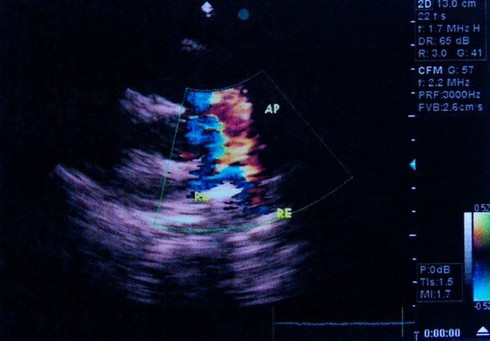

Viêm mạch phổi:Viêm mạch phổi là tình trạng các mạch máu phổi bị viêm, bị tổn thương, dẫn đến vỡ hoặc rò rỉ mạch máu. Ho ra máu là một triệu chứng thường thấy của bệnh tim mạch. |